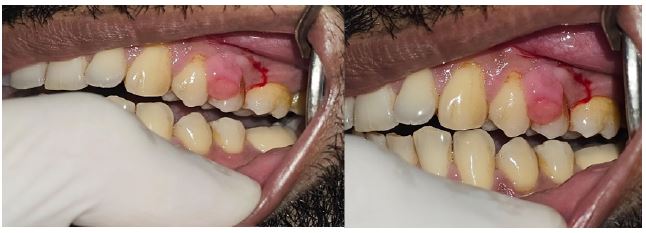

A 43-year-old male introduced to our center with a red, raised sore to his left side lower arm, which had created throughout the last month. He announced gentle inconvenience however kept any set of experiences from getting injury, disease, or hormonal changes. Assessment uncovered a smooth, obvious, 0.8 cm knob with a friable surface. The injury drained upon negligible contact, steady with ordinary attributes of pyogenic granuloma.

The essential indicative methodology included clinical assessment and dermatoscopy, showing trademark vascular designs and a red homogeneous region. An excisional biopsy was performed, affirming the conclusion through histopathological assessment, which uncovered lobular fine multiplication inside a fibromyxoid stroma, reliable with pyogenic granuloma.